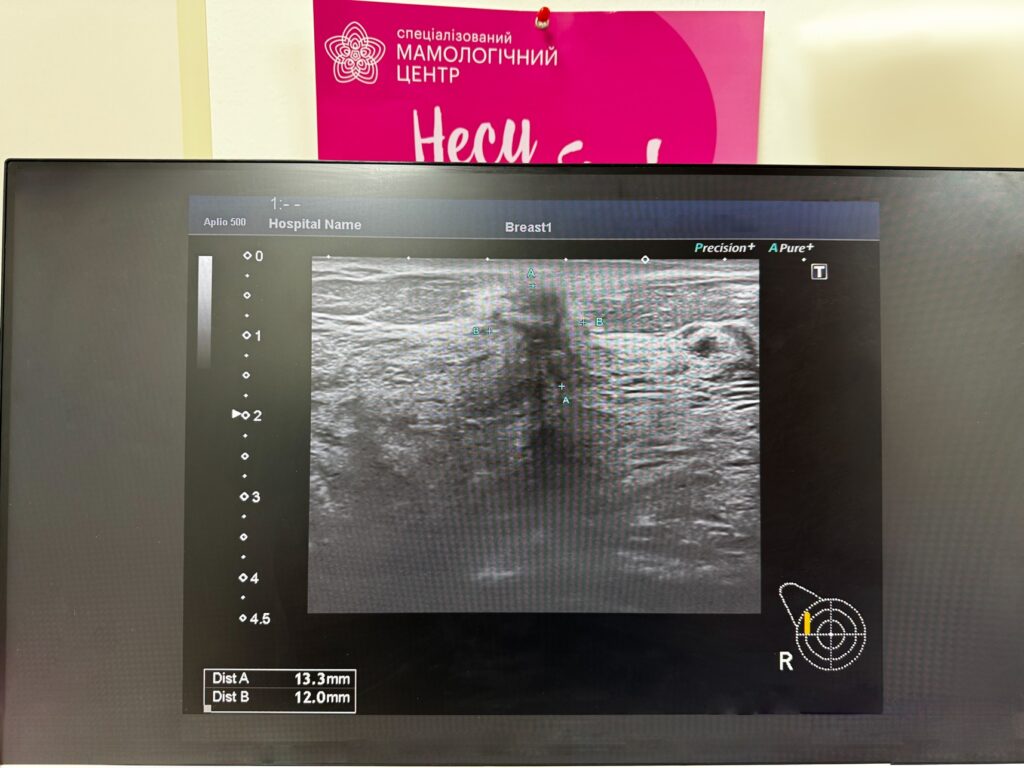

- УЗИ молочной железы – сканирование ультразвуковыми волнами. Как выглядит рак молочной железы на УЗИ – можно увидеть на фото.

Это обычно объемное образование с нечеткими контурами, имеющее вертикальный размер больше, чем горизонтальный. Дополнительные режимы ультразвукового исследования – эластография и допплерография – повышают шансы на выявление злокачественного процесса, в том числе и тех опухолей, которые плохо визуализируются (патологически измененные участки имеют особенности кровотока и другие показатели упругости). - Маммография – рентгенографическое исследование. Позволяет выявить новообразования и другие признаки патологического процесса (например, кальцинаты в молочной железе). Для получения наиболее точных результатов могут проводиться такие виды исследований, как контрастная маммография, маммография с томосинтезом.